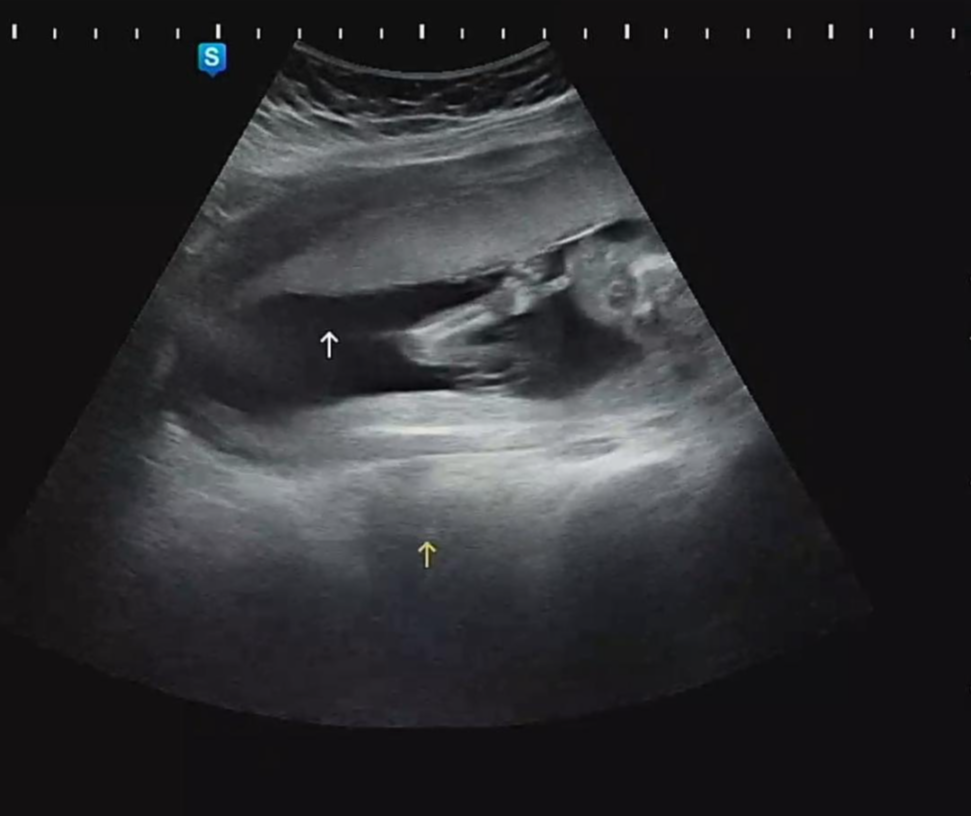

우리 까꿍이의 초음파 영상 중간에 캡쳐를 한 모습. 왼쪽은 손가락을 빨고 있는 듯한 모습과 우측에는 늘씬하게 잘 빠진 다리 각선미를 볼 수 있다.

머리둘레 3.47cm, 배 둘레 10.8cm, 허벅지 2.31cm로 머리, 배 둘레는 16주 차 5일의 평균 수치만큼 발달되었는데 허벅지 길이는 17주 차 수치와 같았다. 롱다리로 태어나길 기대해 봐야겠다^^